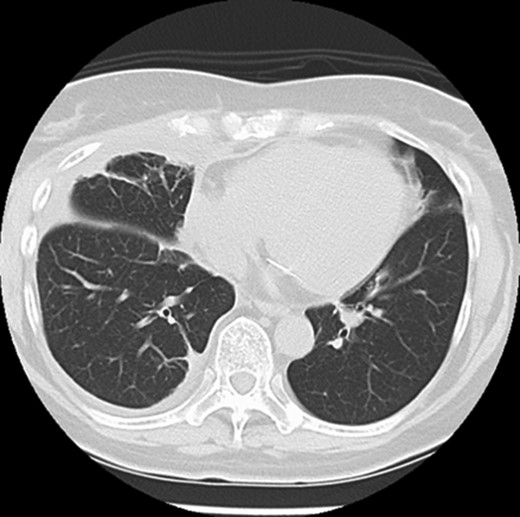

Five days after surgery, she complained of right chest wall pain and discomfort on inspiration. Computed tomography (CT) revealed that part of the right upper lobe of the lung had herniated through the right fourth intercostal space (Fig. 1). Lung hernia was diagnosed. The herniated lung was manually repositioned by compression bandages (Fig. 2). On postoperative Day 11, 6 days after recognition of the herniation, the lung hernia was not apparent on CT. The patient was discharged home without symptoms on postoperative Day 12.